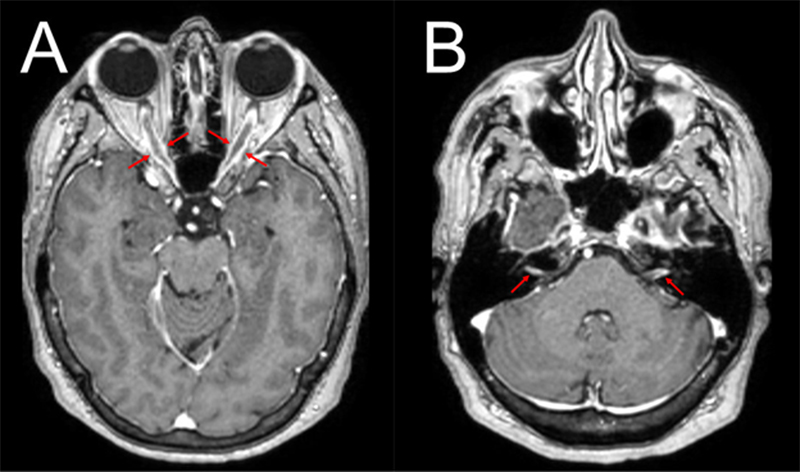

A 68-year-old female with well-controlled hypertension, recurrent urinary tract infections (UTIs), and no history of autoimmune disease presented with progressive, bilateral, painless vision loss, headaches, and bilateral hearing loss. Symptoms began in the left eye before affecting the right eye three months later. Central vision was lost bilaterally, while peripheral vision was only initially preserved in the right eye. The pupillary light reflex on the left was absent, and that on the right was markedly weak. Fundoscopy was normal without optic disc edema or pallor. MRI of the brain and orbits showed circumferential thickening and enhancement of the bilateral optic nerve sheaths, along with left-greater-than-right vestibulocochlear nerve enhancement (Figure 1). Cerebrospinal fluid (CSF) and serum studies were negative for infectious, paraneoplastic, demyelinating, and autoimmune markers, including myelin oligodendrocyte glycoprotein immunoglobulin G (MOG-IgG) and aquaporin4-IgG, with only a non-specific IL-2 elevation in CSF (31.4 pg/mL). Positron emission tomography/computed tomography was negative. The patient only partially improved with corticosteroids and was unresponsive to plasma exchange, rituximab, infliximab, and intravenous immunoglobulin.

Figure 1

A. Orbit MRI (post-contrast axial T1-weighted) revealed circumferential thickening and enhancement of the bilateral optic nerve sheaths (red arrows). B. The same MRI showed circumferential left-greater-than-right vestibulocochlear nerve enhancement (red arrows).